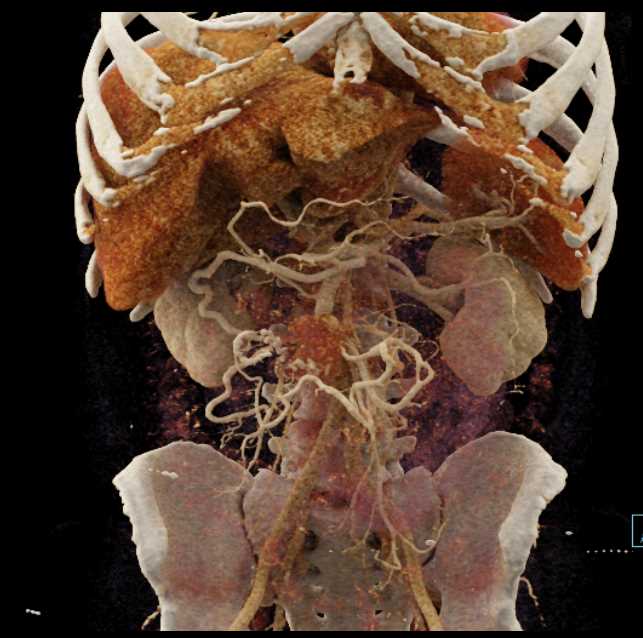

Carcinoid Tumor with Desmoplastic Reaction